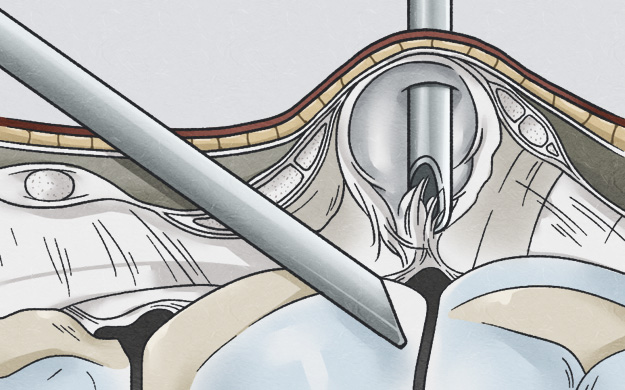

손등의 횡절개 방법은 가장 미용적이며, 상처에 의한 통증도 덜 남는 절개 방법으로 손등쪽 결절종에 경우 대부분 적용 가능합니다.

다음 사진들처럼 수술시 관절에 연결된 뿌리까지 찾아서 제거하여야 재발하지 않기 때문에 수술자의 기술이 특히 중요한 수술입니다.